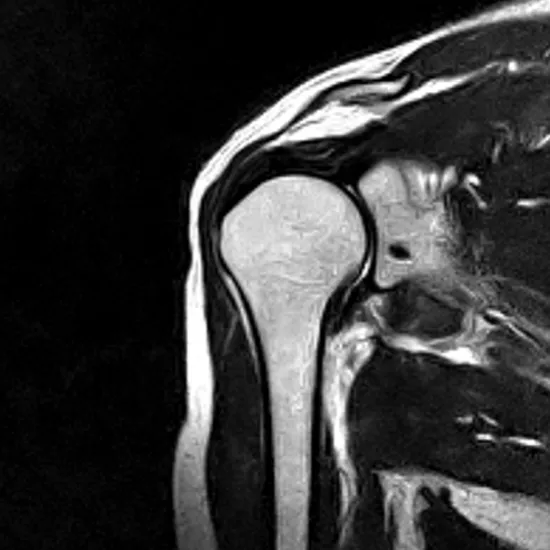

MRI screening of the right shoulder is a non-invasive diagnostic tool that provides detailed images of shoulder joint structures, including bones, tendons, muscles, and blood vessels, from any aspect. The scan lets your doctor view your bones and soft tissues, including your muscles, ligaments, tendons, nerves, and blood vessels.

MRI (Magnetic Resonance Imaging) screening of the right shoulder is a non-invasive radiology test used to evaluate the condition of the Right Shoulder and surrounding tissue. MRI screening of the right shoulder is done to look for its condition and surrounding area.